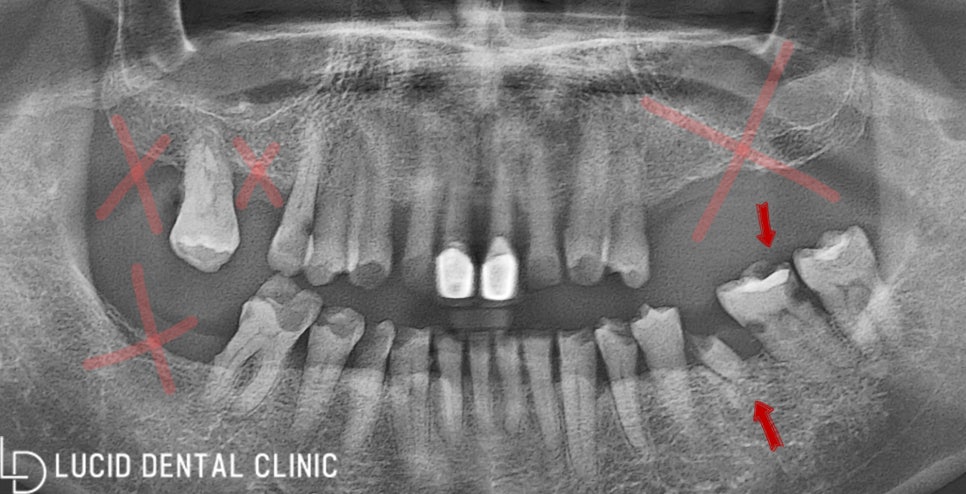

위 사진은 파노라마 방사선 엑스레이로,

구강 모습을 확인할 수 있는데요.

현재 보이는 문제점이 꽤 많아

하나씩 나열해 가며 알려드리겠습니다.

- 치관 소실

여기 표시된 어금니를 잘 보면

충치로 인해 치관이 소실되고 있었는데요.

그뿐만 아니라 근접치까지

우식증이 심한 모습을 보이고 있어

빠른 조치가 필요한 상황이었습니다.

- 비어있는 치아

게다가 중간중간 계속 비어있는

치아 또한 많이 보이고 있는데요.

아까 말씀드린 것처럼

발치 후 오랜 시간 방치하여

치열 변형과 정출이 나타났습니다.

이렇게 되면 교합이 전혀 이루어지지 않아

저작에 큰 불편함을 느끼게 되는데요.